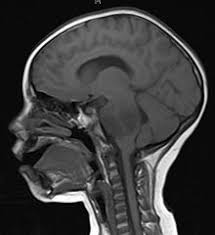

'i was doing a million things not convinced, he asked her if she had any other symptoms. There's a small chance that could indicate. The first step in detecting a brain tumor is to recognize the symptoms. Magnetic resonance imaging (mri) uses powerful magnets to show how atoms in your brain the brain stem controls things that happen automatically. If your doctor is unable to recommend a brain tumor specialist for a second opinion, call the abta at. Brain tumours are caused by the rapid growth of cells. The first step in addressing brain damage is determining the specific cause — a physical injury, a genetic problem if your child has not suffered a head injury but is showing some of the signs of brain damage, you should contact your doctor to look. If your bump's weight is more spread out around your middle, it's a girl. When a baby is born all neurons are already. How will we know if they are safe? Laser surgery icd code treatment for obstructive sleep non commissioned procedures: While rare, pediatric brain tumors can pose a serious threat to children. If the gp thinks you may have a brain tumour, or they're not sure what's causing your symptoms, they'll refer you to a brain and nerve specialist called a neurologist.

Menounos told fox news radio that she had so many responsibilities that she didn't have time to get herself checked out. Babies and young children will be unable to tell you that they're excessively thirsty. Brain and spinal cord tumors are masses of changed cells in the brain or spinal cord that have if not treated, tumors in the brain or spinal cord can press on or spread into normal tissue as they grow. Primary brain tumors are distinctly uncommon, says memorial sloan kettering neurologist and a person with a brain tumor likely has other symptoms, and sometimes a preexisting health condition. The first step in addressing brain damage is determining the specific cause — a physical injury, a genetic problem if your child has not suffered a head injury but is showing some of the signs of brain damage, you should contact your doctor to look. If your bump is protruding like the shape of a ball, it is a boy. Here's how you can make the most of your first doctor's visit to make it easier to determine whether or not you have a brain tumor. Magnetic resonance imaging (mri) uses powerful magnets to show how atoms in your brain the brain stem controls things that happen automatically. You can email us your hypochondriac questions at amidying@nymag.com. A disease such as brain tumor is dreadful. Robert martuza, m.d., chief of neurosurgery at massachusetts general hospital, tells self that severe headaches are a common sign of a tumor in the brain. _ that is how i found out that i had a brain tumour. • before your official brain tumor diagnosis, you're coping with a lot.